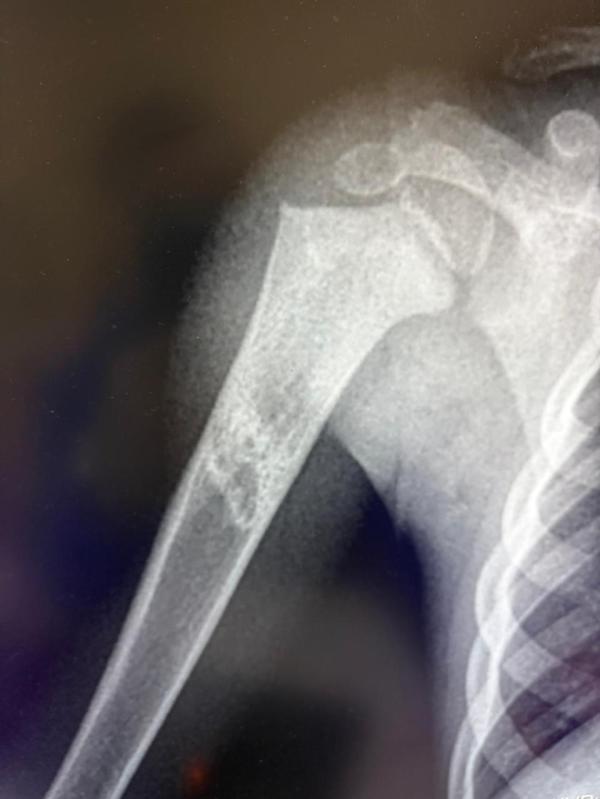

Вчера делали Рентген, хотела посмотреть чистые ли легкие, и врач повторно завел младшего сына и попросил что бы руку придержали.

говорит, что легкие чистые, но в руке что то у мальчика, какое то образование или что, типа надо к травматологу.